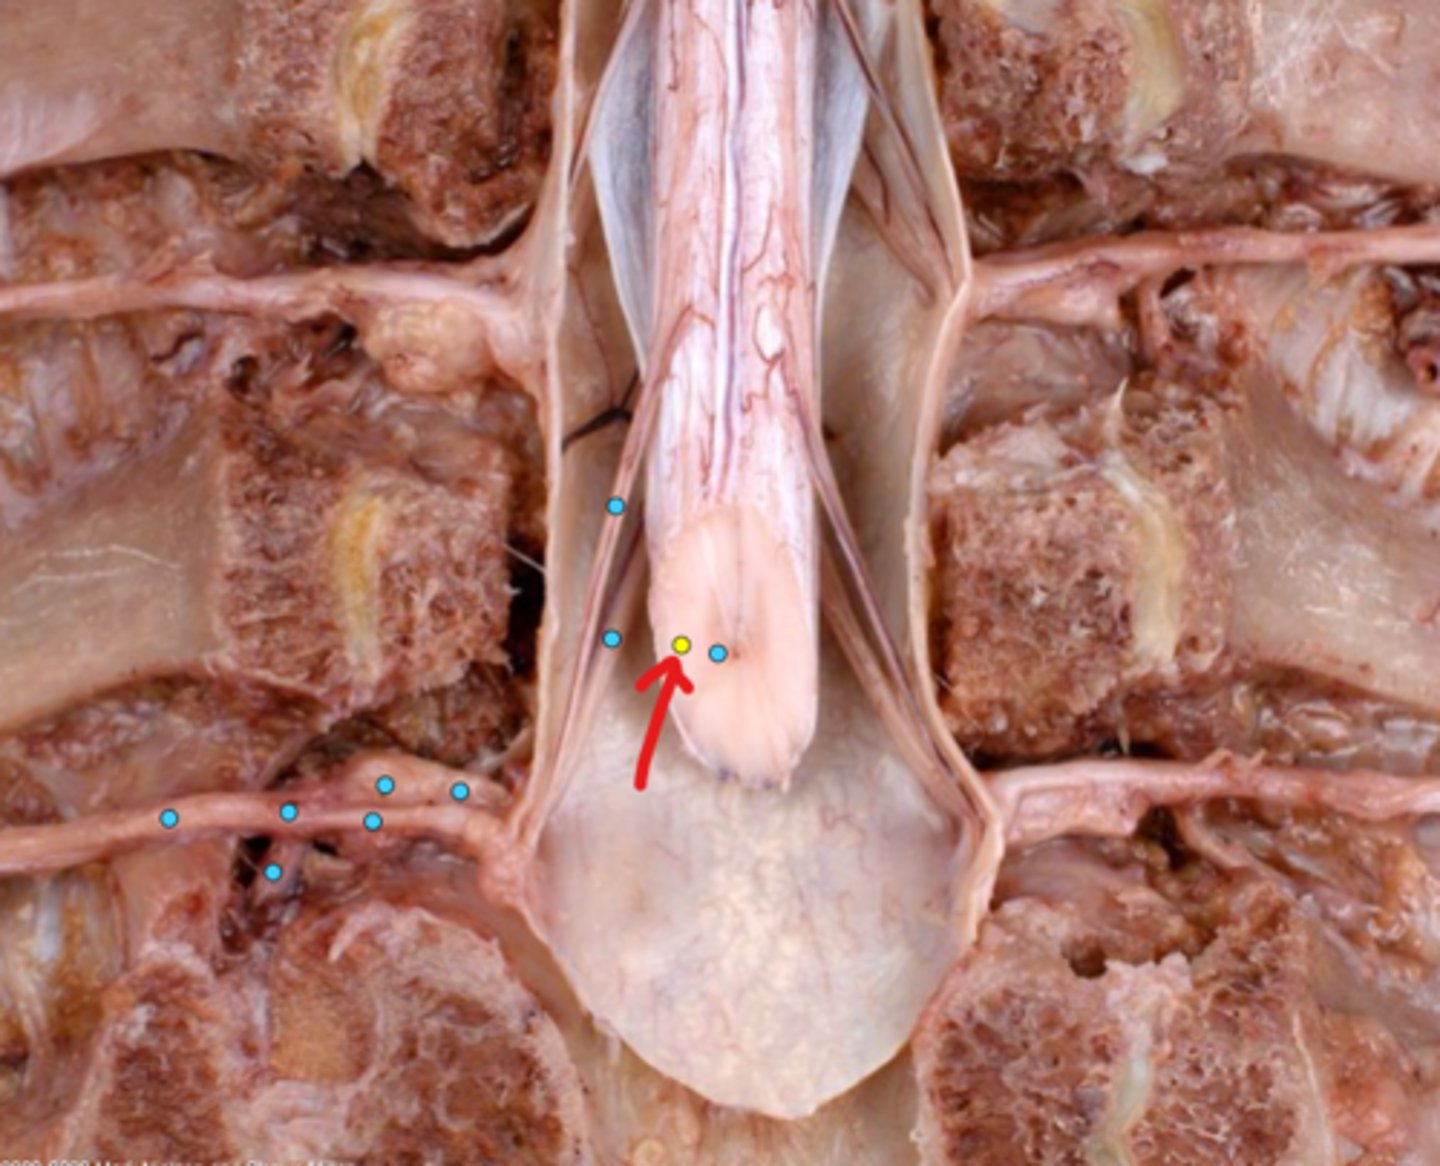

Intercostal nerve

Communicating ramus

Sympathetic trunk ganglion

Sympathetic trunk

Lesser splanchnic nerves

Greater splanchnic nerve

Anterior (ventral) ramus

Spinal nerve trunk

Posterior (dorsal) ramus

Spinal ganglion

Anterior (ventral) root

Posterior (dorsal) root

Anterior (ventral) rootlets

Posterior (dorsal) rootlets

White matter

Gray matter

Posterior (dorsal) rootlets

Anterior (ventral) rootlets

Spinal cord